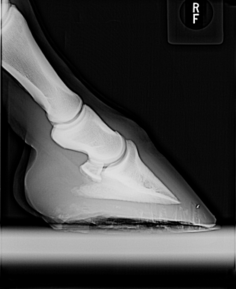

FARRIER LIABILITY

The Farrier Program is designed to respond to the specific insurance needs of the professional farrier.